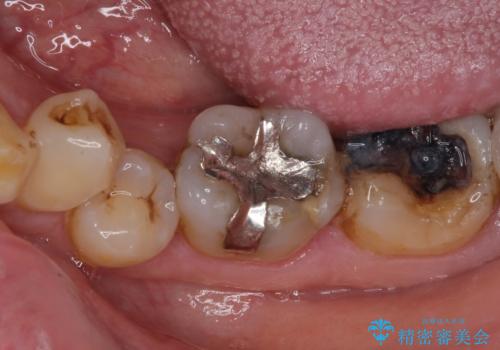

- 銀歯やインレーが外れたまま放置された奥歯の治療を希望して来院された患者様です。

咬合力が著しく強いため、欠損の多い歯はフルジルコニアクラウンへ、その他の虫歯はゴールドインレー(PGAインレー)にて修復することとしました。

来院時は全てセラミックでの治療を希望されていましたが、歯列や咬み合わせから咬合力による破損リスクが高いと判断されたため、ゴールドインレーを選択しました。